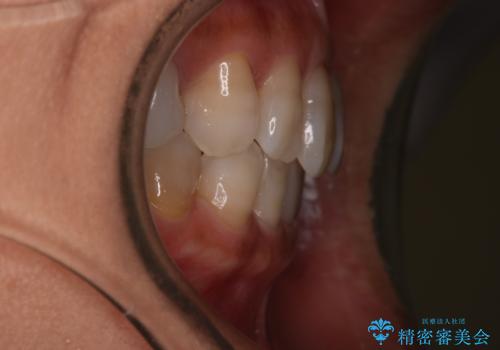

【インビザライン】下前歯だけを治したい

- 下前歯のがたつきにより唇を巻き込んでかんでしまい痛いため矯正をしたいという主訴で来院されました。今回は下顎前歯のみという強い希望があり、下顎のみのインビザライン矯正をしました。

叢生を改善するためのスペースはIPRと拡大を行いました。治療後は唇を巻き込んでしまう主訴が改善し、ご満足していただけました。